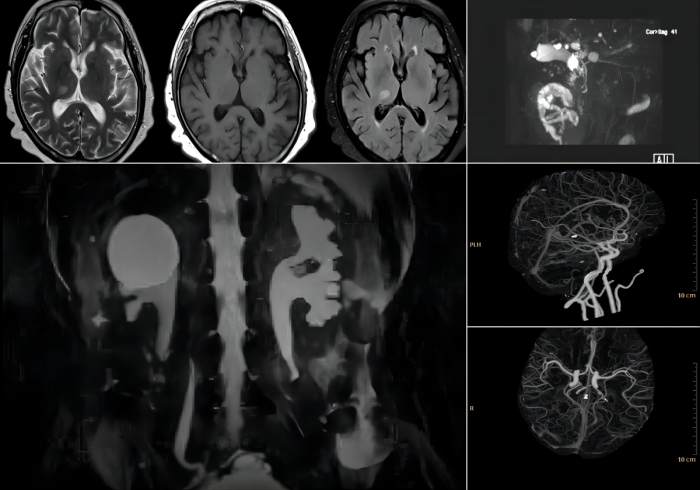

医学影像科现有医疗团队18名,其中医生9名、技术员6名、护士3名,高级职称6名、中级职称4名、初级职称8名,是一支有实力、有活力的专业技术队伍。科室通过开展各项检查,为临床提供可靠的诊断,特别是在神经系统、胸部、全身血管成像、尘肺病诊断等方面积累有丰富的专业实践经验。2022年,与云南省第一人民医院签约磁共振专科联盟。

当前,医学影像科拥有西门子1.5T MR 1台、东芝160层CT 1台、全数字化X线检查机(DR)2台,广泛开展神经、呼吸、心血管、腹部、骨关节影像等检查。作为云南省尘肺病诊断机构,科室开展职业病尘肺检查。

⑶ CT血管造影检查:三维血管图像 从多个角度立体观察血管异常扩张或狭窄的部位和程度;

2.MR检查

⑴功能磁共振成像:包括扩散成像灌注成像、磁敏感加权成像等,可早期发现病变、诊断脑缺血、脑出血进行功能定位等;

⑵磁共振水成像:包括磁共振胰胆管造影(MRCP)以及磁共振泌尿系统造影(MRU)等,代替有创的ERCP等诊断性检查;